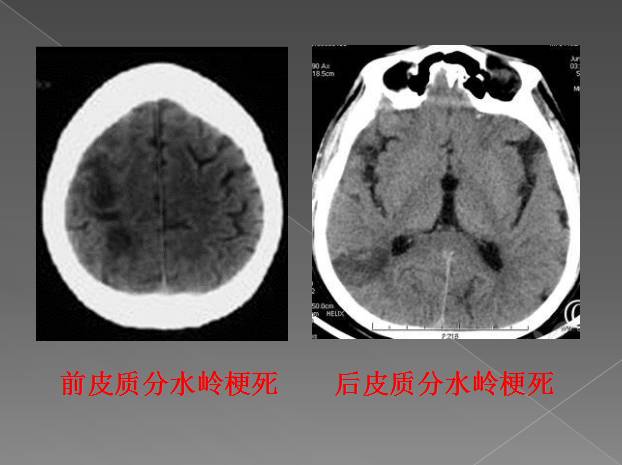

根据供血区域不同,分水岭脑梗分为三型:

1皮质前型

大脑前与大脑中动脉供血区的分水岭脑梗死,位于额中回,呈带状或楔形。临床表现为以上肢为主的中枢性偏瘫及偏身感觉障碍,一般无面舌瘫,可有情感障碍、强握反射和局灶性癫痫。主侧病变可出现经皮层性运动性失语,双侧病变出现四肢瘫及智能障碍或痴呆等。

2皮质后型

大脑中与大脑后动脉或大脑前中后动脉皮层支间的分水岭区。病灶位于顶枕颞交界区,以偏盲最常见,多以下象限盲为主。皮质性感觉障碍偏瘫轻微或无,约1/2病例有情感淡漠,可有记忆力减退,主侧病变出现认字困难和经皮层感觉性失语,非主侧偶见体象障碍。

另外,还有浅表型和深部型之分。该病的诊断并不困难,通过颅脑CT和颅脑核磁共振检查,很容易做出诊断。